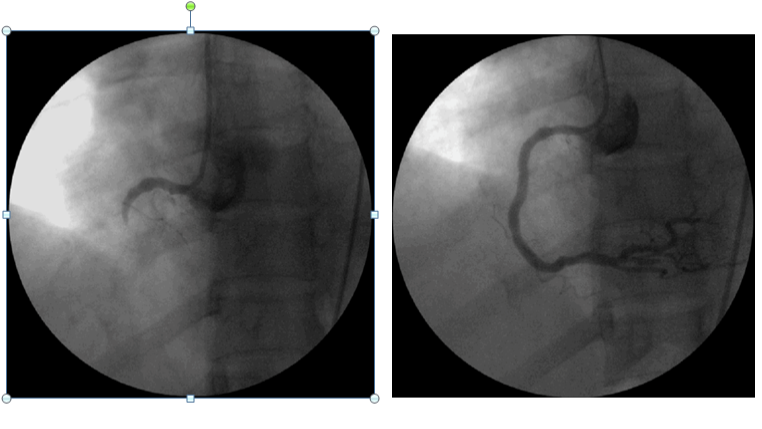

Can thiệp nội mạch cấp cứu một trường hợp vỡ túi giả phình động mạch lách ở bệnh nhân viêm tụy mạn tại Bệnh viện Trường Đại học Y Dược Huế

Bệnh nhân Hoàng Lương T, nam 67 tuổi, được chuyển đến Bệnh viện Đại học Y Dược Huế ngày 15/10/2019 với triệu chứng đi cầu phân đen đã hơn 1 tháng. Bệnh...